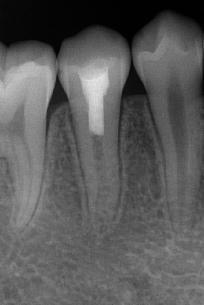

通过牙髓再生治疗,促进牙髓坏死的年轻恒牙牙根进一步发育,牙髓活力测试呈阳性 。

治疗前